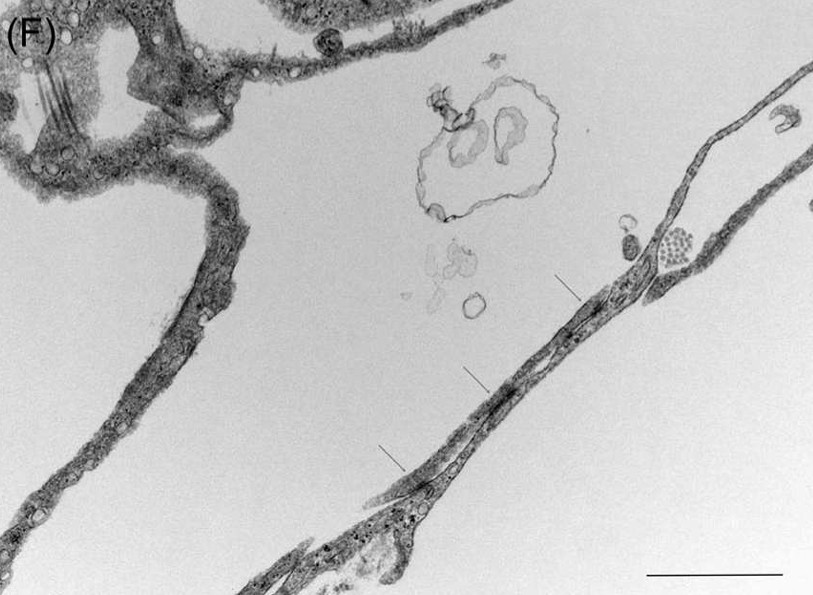

A new paper is published in the medical journal OTO Open. It is titled “Lymphatic Vessels in the Inner Ear of Patients with Meniere Disease: a Novel Pathological Finding”.

This is the first report of lymphatic vessels in the human inner ear, and this pathoogical structure is a completely new discovery. The lymphatic vessels may develop due to inflammation or decomprensation of pressure in the inner ear, suggesting that the inner ear can reactively form lymphatic vessels in some inflammation and fluid-dependent pathological coditions. The current findings help in improving our understanding of the pathogenesis of Meniere disease.